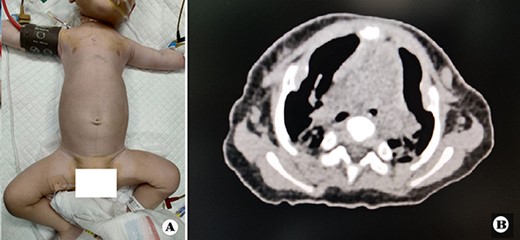

The patient was a female infant born at term with no family history. After birth, the patient developed cyanosis and dyspnea immediately, and emergency intubation and ventilation were performed. One week later, she was weaned and oxygen was given with mask. Oxygen saturation could be maintained basically, but it would decrease when eating and crying. She was eventually diagnosed as ATD and admitted to our hospital to accept surgery four months after birth. Physical examination showed that her chest circumference was 35 cm, and her thorax was narrow and small (Fig. 1A). CT scan revealed that her thorax was deformed, the lateral chest walls were slightly sunken and the lung compression was obvious (Fig. 1B). The operation was performed under general anesthesia. Midsternotomy was made. After the two sternal halves were expanded, three steel bars were placed and fixed on the anterior surface of the sternum (Fig. 2A and B). The bars were covered with pectoralis major muscles, and the skin incision was eventually sutured (Fig. 3A). The chest circumference increased to 40 cm, and the respiratory function was significantly improved postoperatively. Mechanical ventilation was continuously used for 3 days after operation. After weaning, the mask was used for intermittent oxygen supply and stopped 35 days after operation, with the oxygen saturation maintaining above 91%. The patient was discharged 41 days postoperatively. She was followed up for 3 months. There was no hypoxia when calm, but mild hypoxia when crying, which would be relieved after quiet. CT examination 3 months after operation showed that the shape of thorax is improved (Fig. 3B).

(A) Thorax appearance after operation, and (B) CT scan image of thorax after operation.